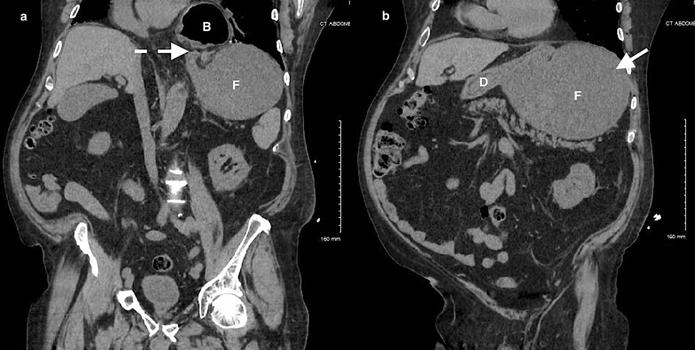

加急CT检查显示中至大型食管裂孔疝和由于胃扭转而呈现的胃部水肿膨胀并伴有部分梗阻(图3-5)。

(图3)

(图4)

(图5)

当怀疑有胃扭转时,选择初始的影像学检查非常重要,因为诊断延迟可能导致致命的并发症。CT检查高度可靠,主要有两种表现,即正常的胃窦幽门移行区和胃窦位置异常,诊断急性胃扭转的敏感性和特异性均为100%。POCUS是一种有效的非侵入性影像检查方式,主要用于床旁评估。此外,POCUS无辐射,并可根据临床情况随时进行重复检查。本例患者POCUS检查显示,胃部严重扩张,胃内容物分层,类似胃出口梗阻(GOO)的“黑白饼干”征象。POCUS还可以用来动态观察胃减压成功与否。